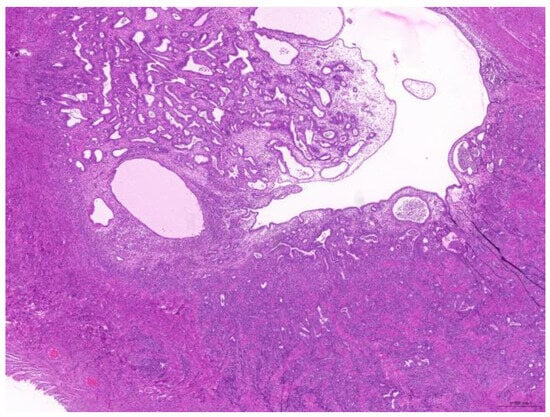

Thirty-six biopsy specimens were taken from the reproductive systems of 22 females and two males (a female-to-male ratio of 11:1). All of the females were intact, and 32 diagnoses were obtained from these 22 females. The median age of the affected females was 71 (20–132) months. The most common diagnoses were uterine adenocarcinoma (50%, 16/32) (Figure 6), followed by endometrial cystic hyperplasia (15.6%, 5/32), uterine adenomyosis (12.5%, 4/32), uterine leiomyoma (6.25%, 2/32), and luteoma (6.25%, 2/32). The median age of the females with uterine adenocarcinoma was 82 (42–132) months. From the two male rabbits, four diagnoses affecting the reproductive system were obtained. Both of these males were intact. The median age of the affected males was 113.5 (109–118) months. The most common diagnosis was interstitial cell tumor (50%, 2/4), followed by seminoma (25%, 1/4) and testicular atrophy (25%, 1/4).

Figure 6. Uterine adenocarcinoma. The neoplasm effaces the original uterine structure (scale bar = 500 µm). Hematoxylin and eosin staining.